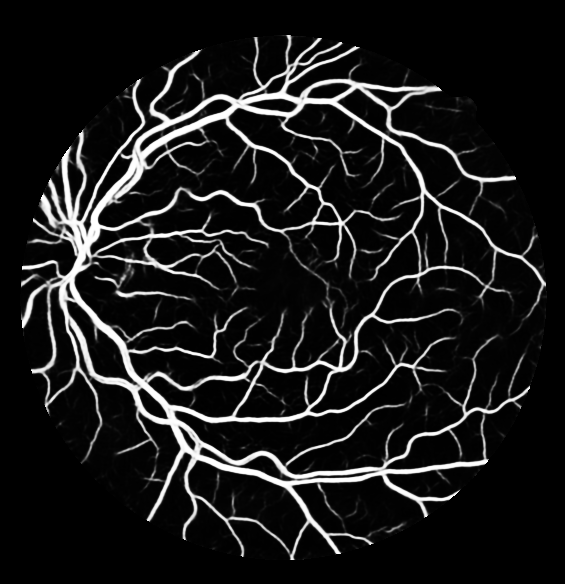

The evaluation of each experiment over the five different initialization roll-outs are reported in Table 1-4. The mean and standard deviations of five commonly used metrics, namely specificity, sensitivity, F1 score, accuracy and the AUC score are presented. The threshold for binarization is selected such that the F1 score is maximized on the validation sets. The threshold independent AUC score is chosen as the main performance indicator. The output probability maps of the degenerated trials are presented in Fig. 2 (c-f).